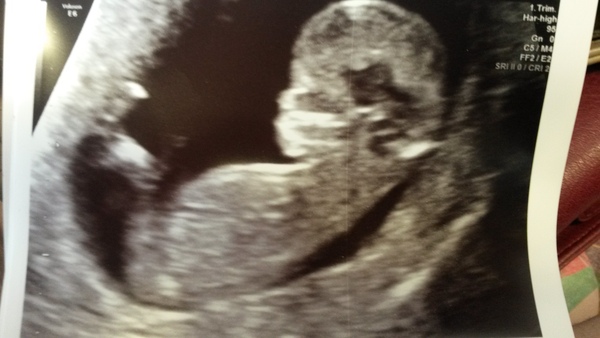

Good news at my scan yesterday, dated 12 weeks exactly so due 21st April. Unfortunately I couldn't have the nuchal test I wanted as baby wouldn't move into the right position, so have to go back for the quadruple blood test in a few weeks instead. Everything looked fine though :) I am so relieved.